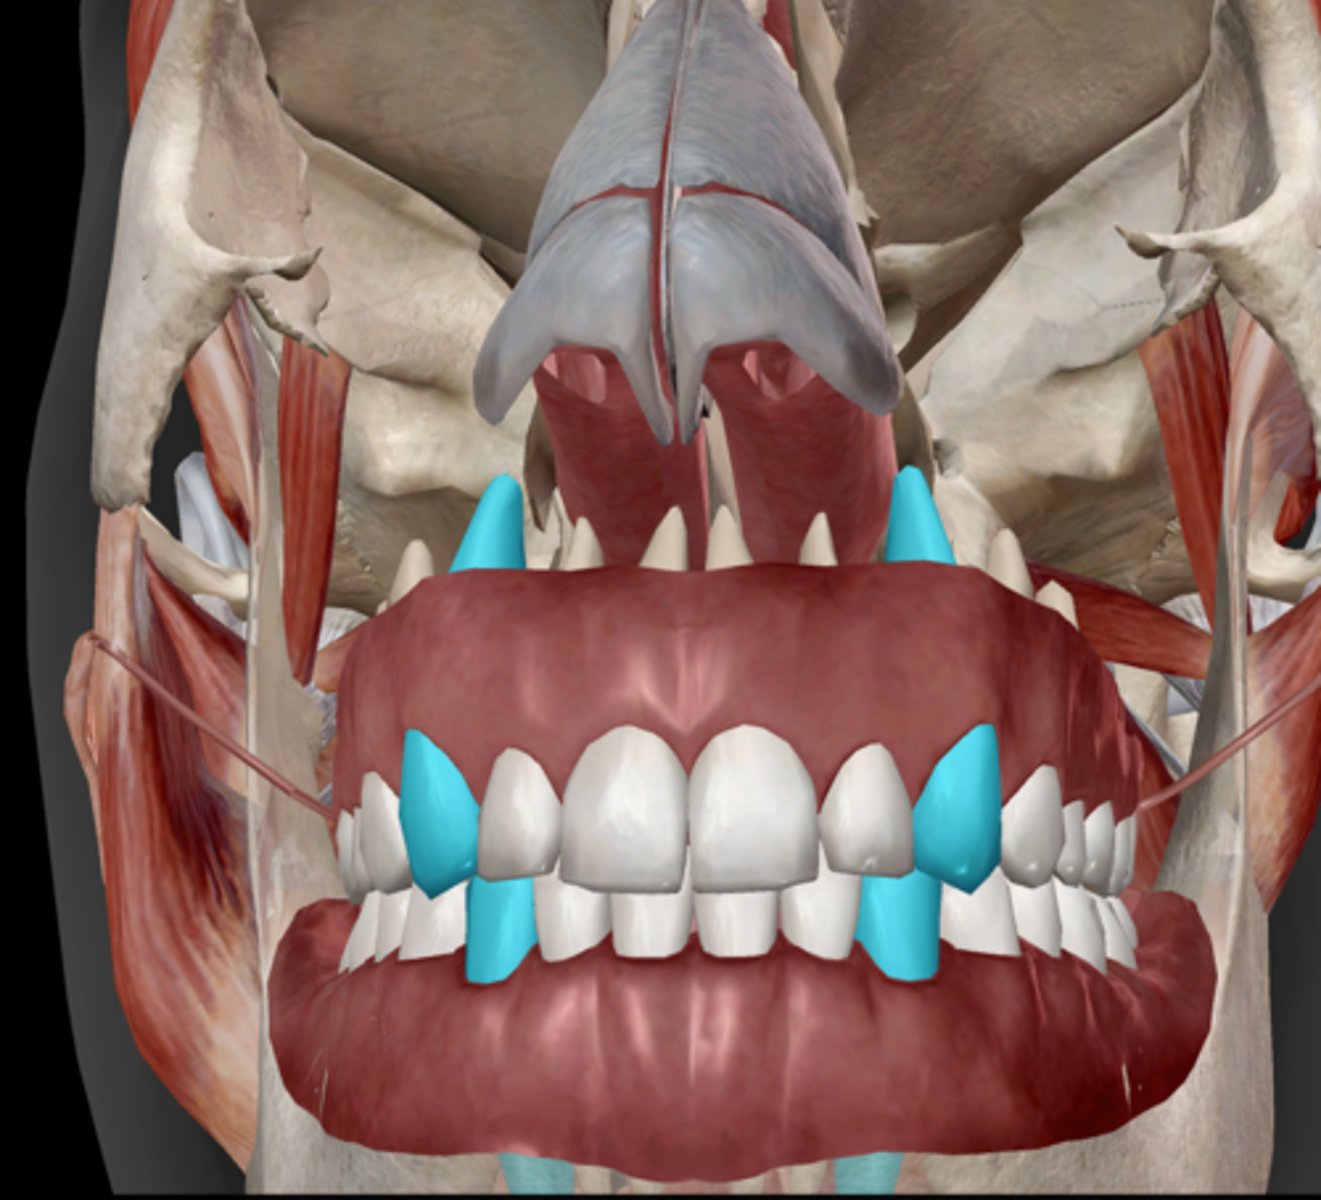

Incisor

Canine (cuspid)

Premolar (bicuspid)

Molars